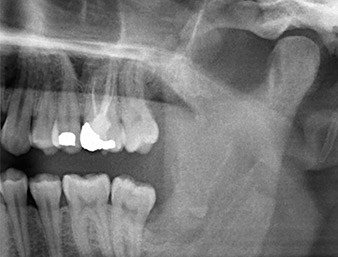

El tejido situado por encima del resto radicular no se había osificado por completo y constaba en su mayor parte de un tejido granulado con alteraciones inflamatorias (figura 4).